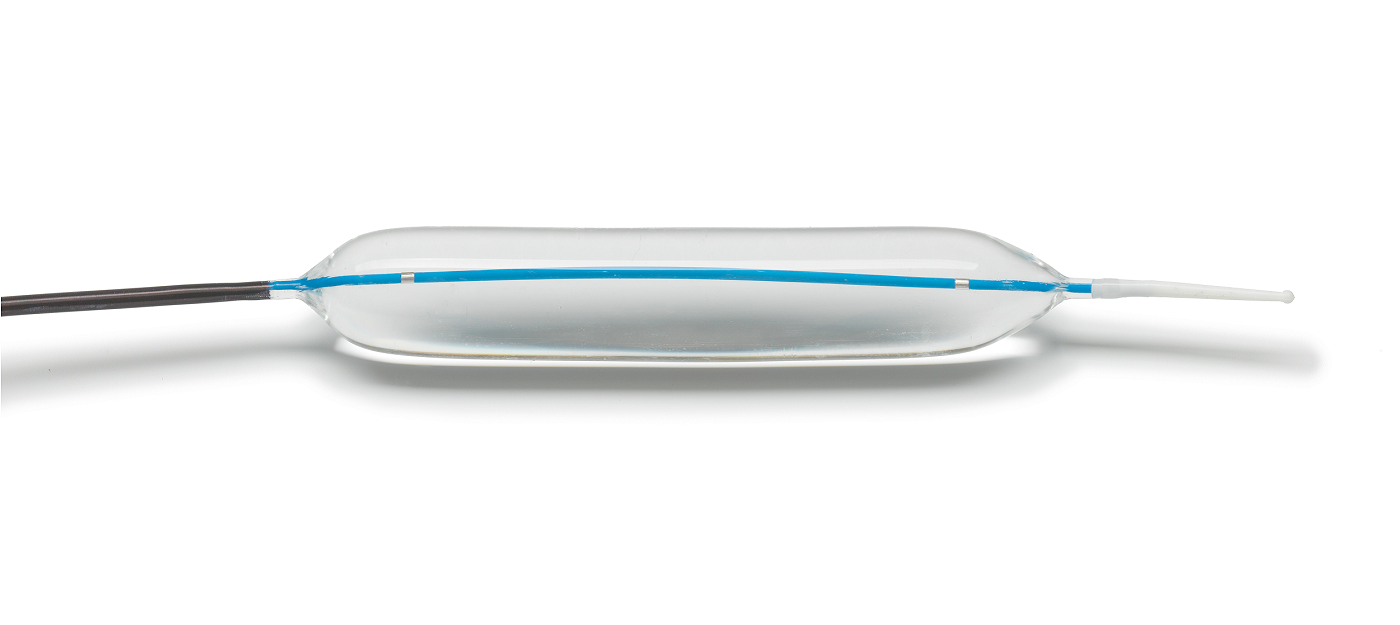

HEART ATTACK

A heart attack, also known as a myocardial infarction, occurs when heart muscle doesn’t receive enough blood. As time passes without receiving treatment, the more damage is done to the heart. The main cause of a heart attack is coronary artery disease (CAD). Researchers have found that throughout life, men are about twice as likely as women to have a heart attack.

Learn more about heart attacks. Explore our Cardiac Portfolio, including our radial sheaths, catheters, wires, and compression devices.

MERIT PRODUCTS